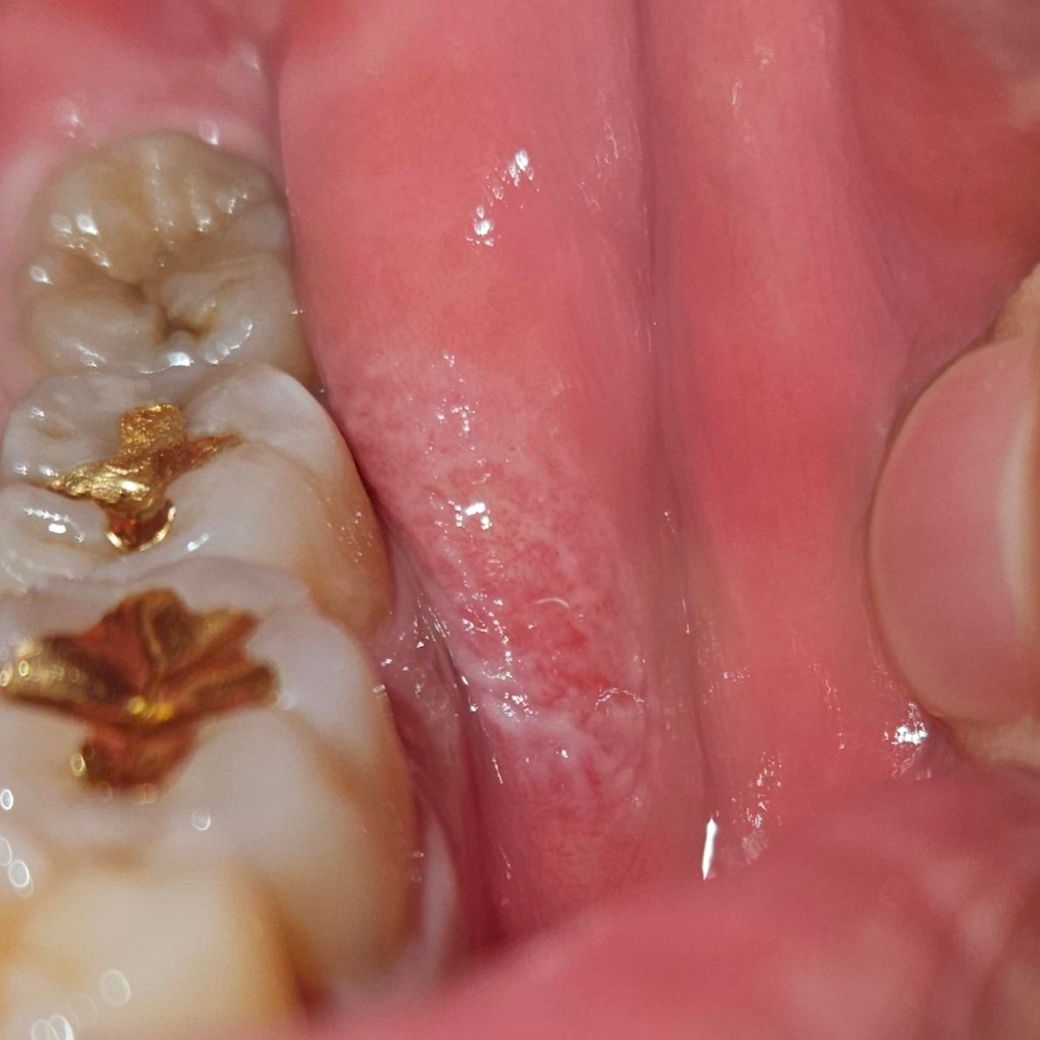

어금니쪽 구내염 호전되고 있는 건가요?

3주째 안 나아서 금요일부터 치과 진료받고 페리덱스 처방 받아 약 바르고 있습니다.

육안으로 봤을 때 아물고 있는 것 같긴한데 전문가 분들이 봤을때 차도가 있는 게 맞는지 궁금합니다.

왼쪽 볼이랑 어금니기 계속 닿는 것 같긴하더라구요..

순서대로 10일 전 사진 어제 사진 오늘 사진입니다

사진으로 보아서는 점점 좋아지고 있는 것으로 보여집니다. 페리덱스를 처방 받은 이후에도 증상이 호전되지 않는다면 대학병원의 구강내과를 방문하여 해당 부위의 연조직 질환이 무엇인지 정확히 조직검사를 해보는 것이 좋을 수 있어 보입니다.

사진으로 명확히 알기는 어려우나 조금씩 호전되고 있어 보이며 약 효과는 좋은 편이니 계속 쓰시면 됩니다.

구내염은 자극을 주지 않으면 괜찮아 지실꺼에요. 상처도 호전되고 잇으니 걱정하지 않으셔도 될것같습니다.

사진상 호전이 되고 있는 것으로 보이며, 소독용 가글인 헥사메딘 가글액도 함께 사용시 증상 경감에 보다 효과적입니다.